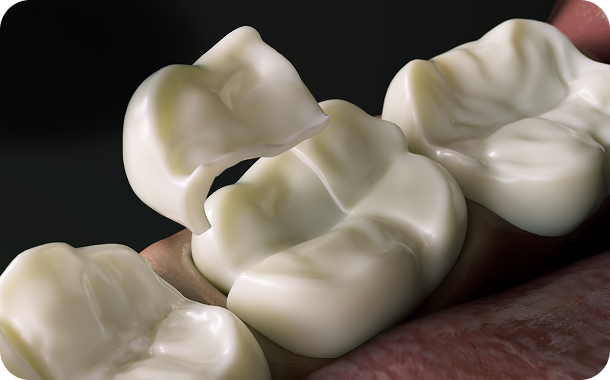

단순한 치료를 넘어 일상의 완성을 설계하는

통합 진료 솔루션

단순한 치료를 넘어 환자의 마음을 헤아리는 것에서 연세아이돌치과의 진료는 시작됩니다.

치과교정과 전문의의 심미적 안목과 통합치의학과 전문의의 포괄적 진단이 만나는 곳.

연세아이돌치과교정과의 일반진료는 단순히 질환 부위만을 바라보지 않습니다.

치아 하나가 전체 구강 구조와 조화를 이루는지,

환자분의 식습관과 생활 패턴에 장기적으로 어떤 영향을 미칠지까지 치밀하게 계산합니다.